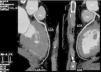

To clarify the clinical picture and since he was considered to have a low to intermediate likelihood of coronary artery disease, and also bearing in mind his physical limitations, he was referred for cardiac CT to rule out coronary artery disease. The exam showed a left coronary artery arising from the right coronary cusp and with an interarterial course, between the aorta and pulmonary trunk (Figures 1–3). No coronary plaque was detected and his calcium score was 0.